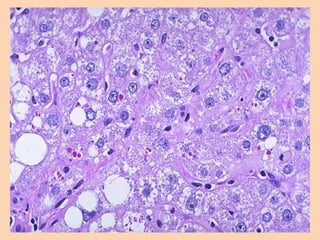

Alcoholic hepatitis :Develops acutely after the bout of heavy drinking ,

Histologically

• Hepatocellular necrosis :

in centrilobular zone

• Ballooning degeneration

• Mallory bodies

eosinophilic

intracytoplasmic hyaline

inclusions represents

(aggreagates of

intermediate filaments)

• Inflammatory infiltrate

• Fibrosis: pericellular

and perivenular